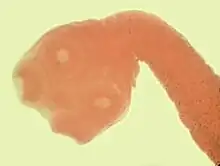

Cisticerco

O cisticerco da Taenia solium é constituído de uma pequena bexiga, que deixa a luz passar, com líquido translúcido. Dentro dela, existe uma cabeça de tênia com as quatro ventosas com rostelo e colo já formados. Taenia saginata é semelhante, porém, não contém rostelo.